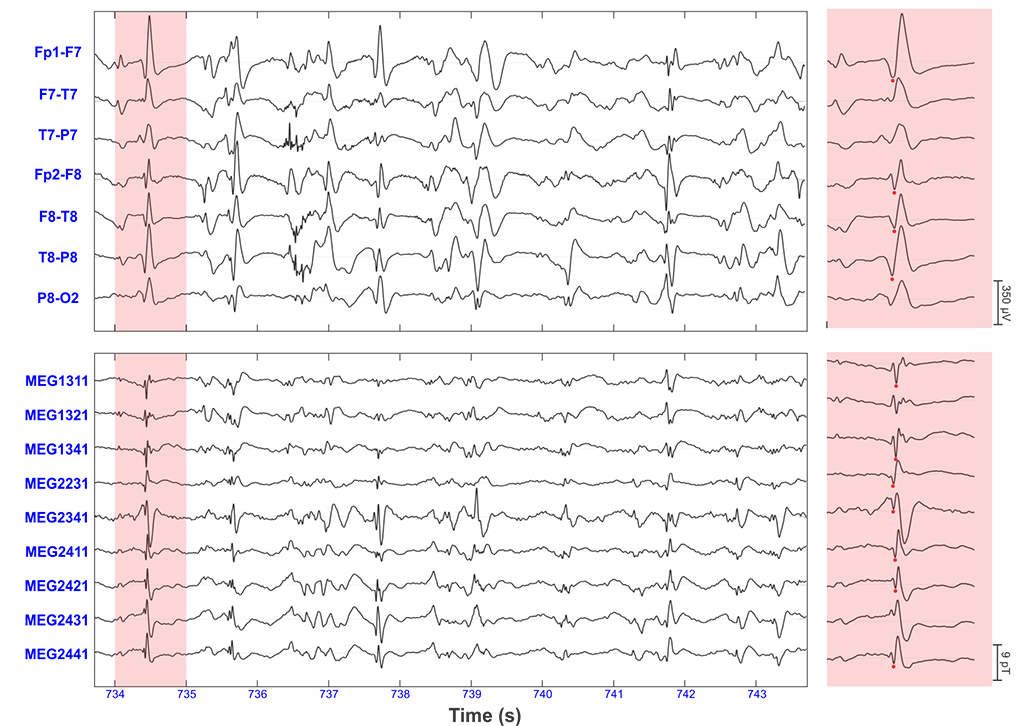

Yet, the results of these tests are sometimes inconclusive or contradictory. Thus, new techniques and data analysis methods need to be developed in order to help reliably identify the epileptogenic zone. Funded by the National Institute of Neurological Disorders and Stroke, our research team led by Dr. Christos Papadelis (Principal Investigator) works closely with our epilepsy medical team at Cook Children’s Health Care System (Dr. Scott Perry and his team) and collaborators at Boston Children’s Hospital (Dr. Phillip Pearl and his team) and Massachusetts General Hospital (Dr. Steven Stufflebeam and his team) to develop such new biomarkers. The team focuses its efforts on signals which seem to be generated particularly by the epileptogenic zone. These signals are called high frequency oscillations (or HFOs) and are characterized by fast oscillatory activity in the frequency range between 80 and 500 Hz. HFOs can be recorded using invasive techniques such as stereotaxic electroencephalography (sEEG), but our group has shown strong evidence that HFOs can also be recorded non-invasively using scalp electroencephalography (EEG) or magnetoencephalography (MEG) (Fig. 4 - left) (see Papadelis et al., 2016; Tamilia et al., 2017; Tamilia et al., 2020). Figure 4 (right panel) shows an example of an HFO detected non-invasively with EEG and MEG. The development of such a non-invasive biomarker of epilepsy would augment the presurgical evaluation of children with refractory epilepsy by guiding the placement and implantation of intracranial EEG and facilitate the surgical planning for these patients.